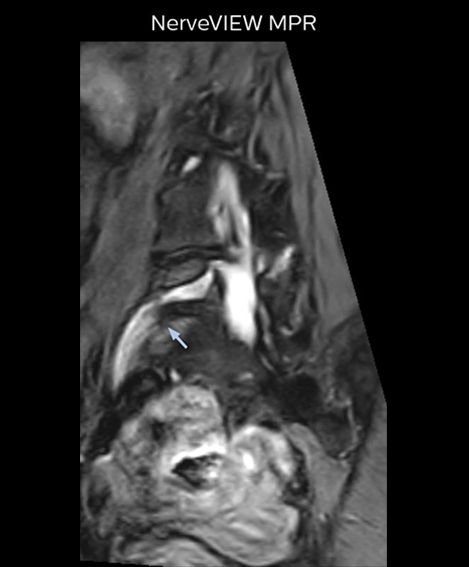

The key concept in MR neurography, Dr. Yabuki stresses, is the ability to directly visualize spinal nerves, versus inferring the presence of pathology indirectly. “Before NerveVIEW, we estimated compression of the nerve by looking for the presence or absence of fat signal on other MR images,” he says.

“For example, in sagittal images, when the presence of fat is observed in the intervertebral foramen, it suggests that there is a margin around the nerve. Similarly, the absence of fat indicates that the nerve is being compressed. So, we used to deduce nerve compression indirectly. With NerveVIEW, however, we can observe the condition of the nerves directly, regardless of the presence or absence of fat. We always prefer such direct observation of anatomy over having to make an inference about it.”

“Although symptoms of typical disc herniation and atypical hernia are very similar, the actual site of herniation is different. It is therefore important to characterize the nerve’s condition both inside and outside of the intervertebral foramina. “Conversely, if we see no abnormality in NerveVIEW, we can assume at least that there is no severe condition that requires surgery. Like this, it can help us avoid unnecessary surgery. NerveVIEW can have a tremendous impact in this way.”

“The intra-luminal signal of veins, especially around the intervertebral space, can be suppressed well with NerveVIEW. As a result, we can easily observe the detailed nerve structure around the posterior ganglion,” he says. “This is why we use 3D NerveVIEW for intraforaminal stenosis and extraforaminal stenosis/herniation (lateral disc herniation). On the other hand, if herniation is suspected to exist inside the dorsal root ganglion (DRG), balanced TFE or ProSet-FFE is applied. NerveVIEW is not suitable for evaluating the median type of herniation.” The SE-EPI DWI-based method for MR neurography works well for large FOV exams like whole-body MRI, but focal examination of nerves is often limited by the attainable spatial resolution (both inplane and slice direction) and geometric distortion. “3D NerveVIEW achieves higher in-plane resolution – close to our other routine spine sequences – and the source images can be used instead of adding a fat-suppressed T2-weighted sequence,” Tanji says.